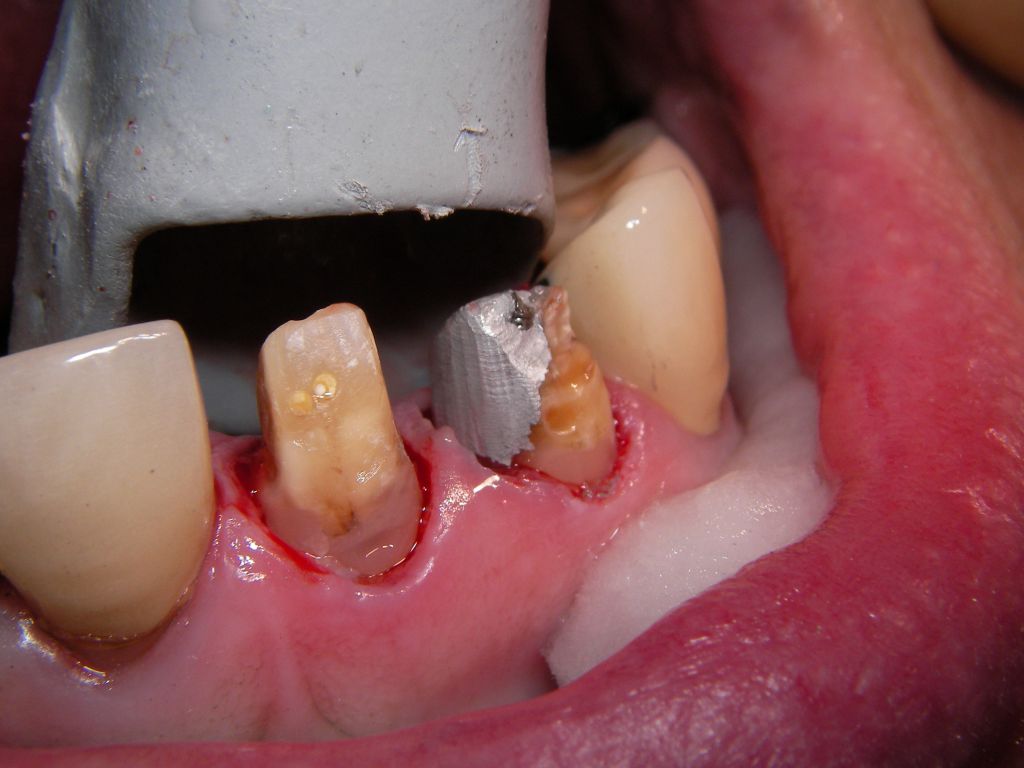

Weil auch die anderen Schneidezahnkronen (12-22) durch Randreparaturen und den schlechten Randschluß erneuerungsbedürftig aussahen, wurden 4 Einzelkronen geplant. Vorher hieß es aber noch, die schlechte Wurzelfüllung im Zahn 12 (Röntgenbild links) besser zu machen. Hierfür wurden am 17.2.06 die alten Kronen 11 und 12 entfernt. Rechts das Bild nach Entfernung von alten Füllungen und Karies.

Links nach Wurzelfüllung beim Einpassen des Titanstiftes. Rechts dann der schon provisorisch beschliffene Amalgamaufbau im Zahn 12.

Links das Kontrollfoto nach der Sitzung am 17.2.06. Damit war die Vorbehandlung in diesem Fall abgeschlossen. Am 28.2.06 erfolgte die endgültige Präparation (das "Beschleifen") aller 4 Zähne. Links das Modell, auf dem die Kronen gefertigt worden waren. Rechts kurz vorm Zementieren der Kronen am 13.3.06. Aus der Längendifferenz der Zähne rechts und links kann man darauf schließen, daß die Präparation tief unter dem Zahnfleisch erfolgen mußte.